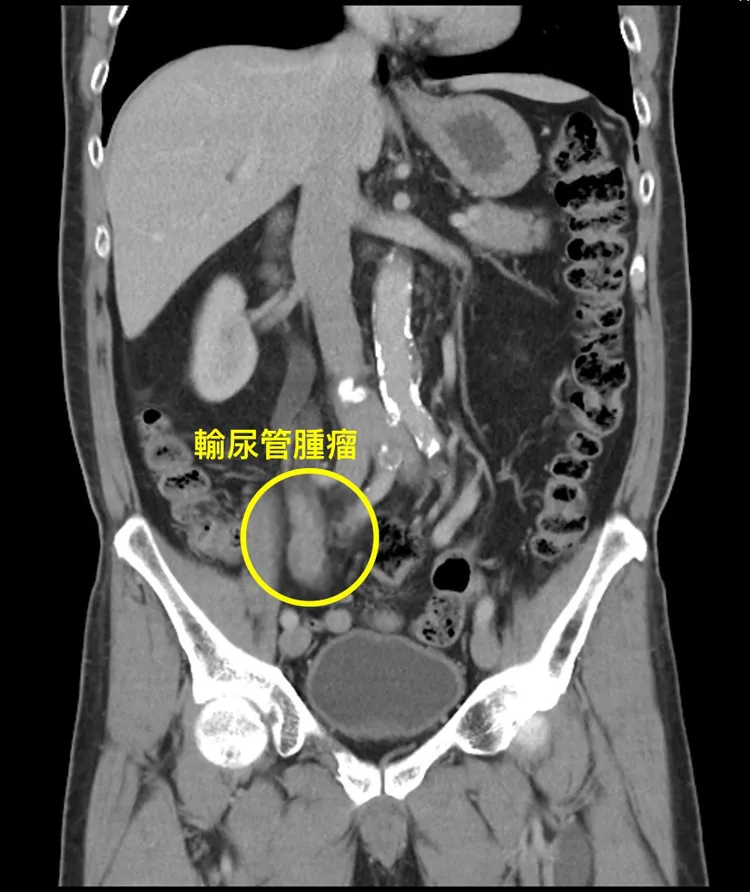

65歲的童先生到光田醫院求診時,腎臟科張家築副院長考量病患已長時間未追蹤病情,為其安排整體性檢查,從尿液檢查得知童先生有顯微性血尿的症狀,此外,腎臟超音波更發現右側腎臟已屬重度腎水腫,且他沒有明顯疼痛,反而更危險,先進行X光檢查後排除結石問題,再為其進一步安排腹部電腦斷層探知,右側輸尿管中段有明顯腫瘤,便安排泌尿科會診,後續做完輸尿管內視鏡切片方確診為上泌尿道上皮癌。

經檢查發現童先生右側輸尿管中段有明顯腫瘤。院方提供